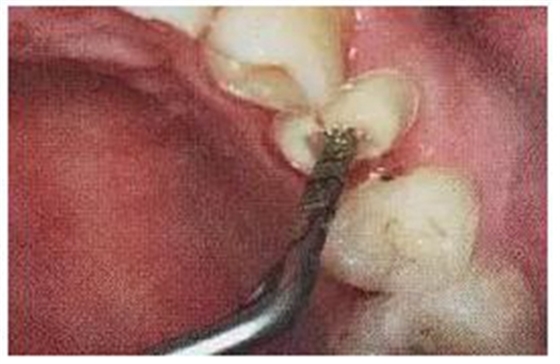

13.不規(guī)則根管的纖維樁粘接

普通纖維樁對圓形截面的根管適合性較好,面對不規(guī)則時(shí)(橢圓形、喇叭形等)根管適應(yīng)性差,難以取得好粘接和修復(fù)效果。

(輔樁的運(yùn)用)

輔樁的運(yùn)用可改善這些適應(yīng)性的問題。

(ELLIPSON 技術(shù))

ELLIPSON

技術(shù),采用超聲預(yù)備鉆對扁圓形根管進(jìn)行直接預(yù)備,改善了樁核根管的適應(yīng)性。有效的保存了根管牙體組織,從而增強(qiáng)了粘接面積,,減少樹脂水門汀的厚度,提高根管內(nèi)纖維樁的粘接強(qiáng)度。